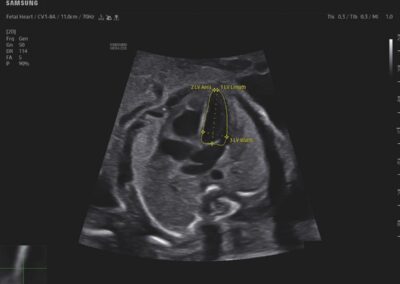

Procedural Services

Comprehensive, advanced and expert MFM care for high-risk pregnancies